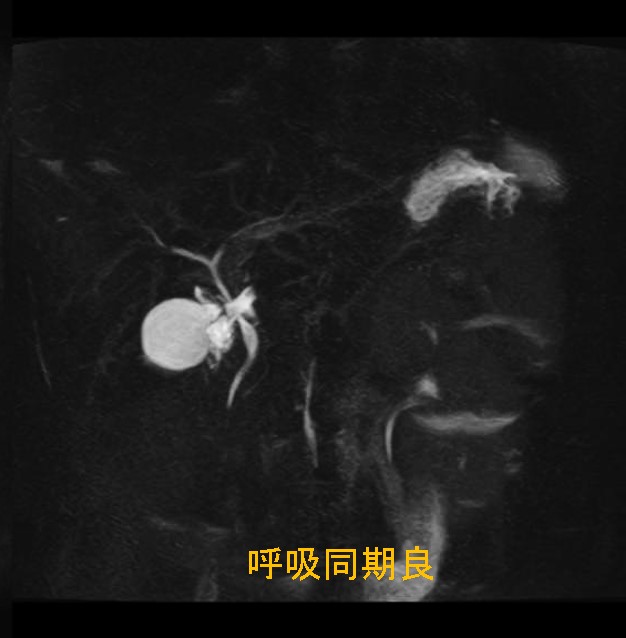

はじめまして、初投稿をさせて頂く獨協医科大学越谷病院 放射線部 大橋一範です。 今回、磁化率アーチファクトの抑制テクニックであるWARPアプリケーションについて語りたい思います。初代WARPアプリケーションではView Angle Tilting(以下、VAT)法を使用しています。